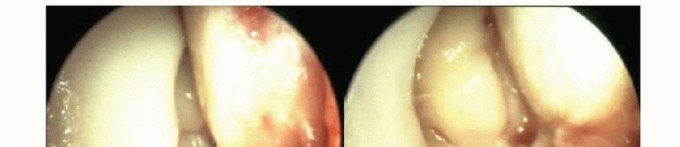

Ligament lesions are graded as distended if the ligament is thinned or elongated and as ruptured if

continuity is lost.8 Most ligament tears are located on the proximal insertion; this is best seen by a completely free insertion area of the ligament on the malleoli (TECH FIG 1).

As the foot is everted and pronated, the deltoid ligament is considered incompetent when it is tensioned, but obviously, no strong medial buttress is created with this maneuver (TECH FIG 2). An excessive lifting away of the talus from the medial malleolus by pulling the foot anteriorly is also considered an indicator of stretching of this ligament.

- TECH FIG 1 • Avulsion of the anterior superficial layers from the medial malleolus. Arthroscopy typically reveals a completely free insertion area of the ligament on the medial malleolus.

- TECH FIG 2 • Incompetent deltoid ligament. A. As the foot is everted and pronated, the deltoid ligament is considered incompetent when it is tensioned, but obviously, no strong medial buttress is created with this maneuver. B. An excessive lifting away of the talus from the medial malleolus by pulling the foot anteriorly is also considered an indicator of stretching of this ligament.